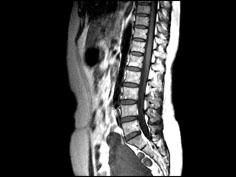

问题 女,37岁,下腹部不适,MRI检查如图所示,下列说法不正确的是 ( )

选项 A、此为子宫粘膜下肌瘤 B、此为子宫浆膜下肌瘤 C、病灶T1信号与子宫肌的信号相同 D、病灶T2信号为明显低信号 E、子宫底部局部隆起,该病灶边界清晰

答案 A